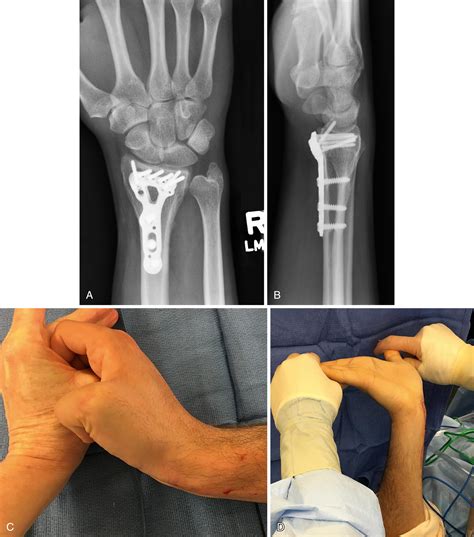

For established, severe contractures, surgical reconstruction may be necessary to improve hand functionality. Common procedures include:

• Tendon Lengthening: Relieving the tension on the shortened flexor tendons to allow for improved wrist and finger extension.

• Muscle Slide Procedures: Detaching the origin of the contracted muscles to allow them to sit in a more relaxed, elongated position.

• Free Muscle Transfers: In cases of massive muscle loss, a muscle from another part of the body may be grafted to restore active motion.